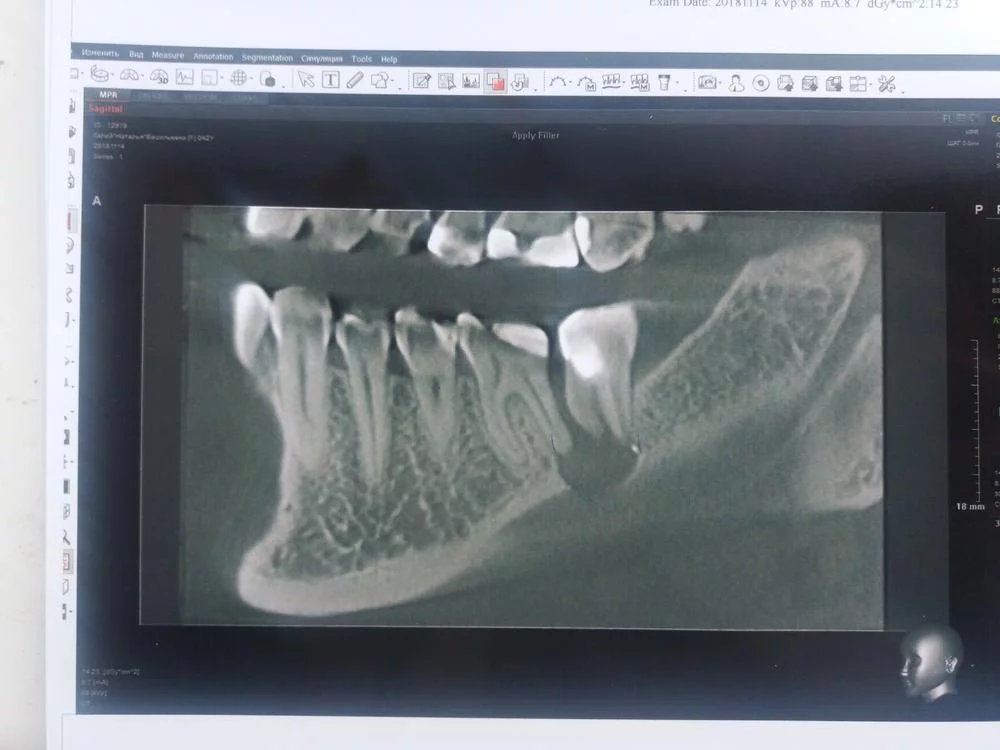

Пародонтолог в такой ситуации может не взяться. Считается, что случай запущенный.

А что же делать в такой ситуации ? Посоветуйте пожалуйста. Пока я прошла курс электрофореза, и чувствительност уменьшилась